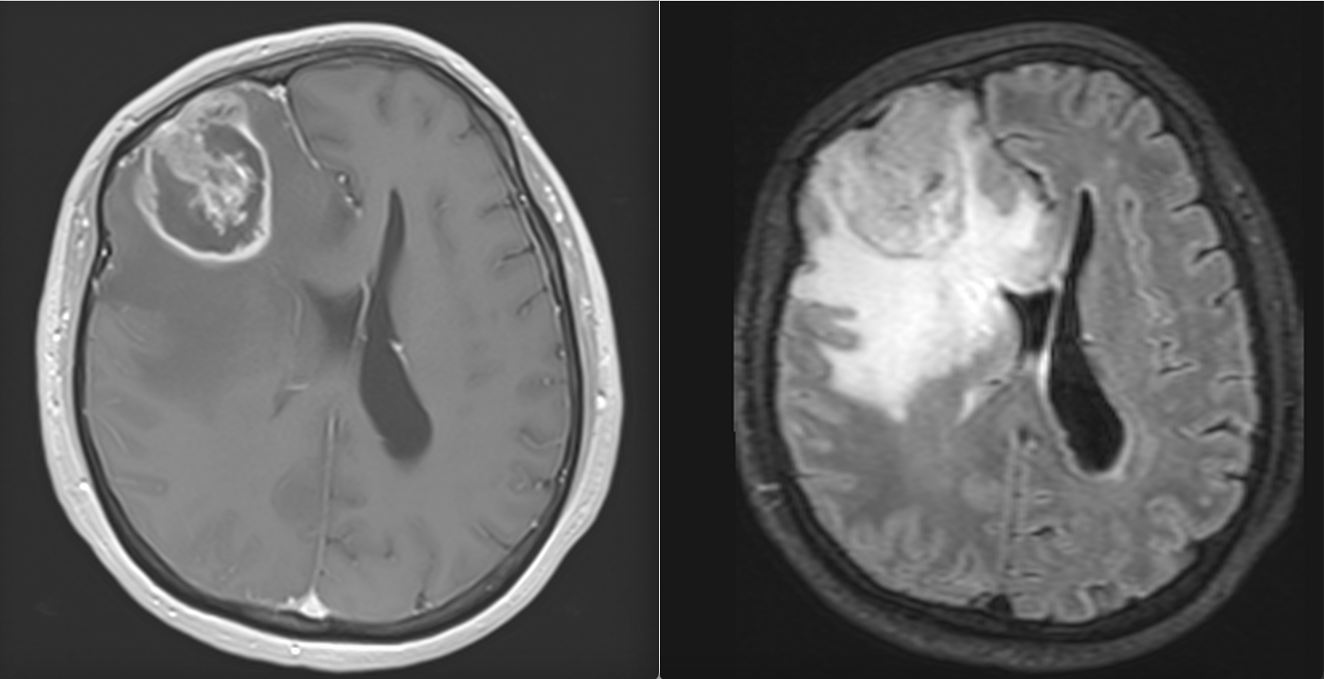

La nivel imagistic, glioblastomul apare adesea ca o leziune relativ bine delimitată, cu captare inelară de contrast și necroză centrală. Pentru ochiul neavizat, aceasta poate sugera o tumoră care ar putea fi „scoasă complet”. În realitate, ceea ce vedem pe RMN reprezintă doar componenta cea mai densă tumoral.

Imagistica – instrument esențial, dar imperfect

RMN-ul cerebral este standardul diagnostic, dar trebuie interpretat în context.

Pe lângă secvențele convenționale, tehnicile avansate aduc informații suplimentare:

- perfuzia evidențiază angiogeneza tumorală

- spectroscopia reflectă metabolismul celular

- DTI (tractografia) arată relația cu tracturile din substanța albă

Cu toate acestea, niciuna dintre aceste metode nu poate delimita complet infiltrarea microscopică. De aceea, planificarea chirurgicală și terapeutică trebuie să țină cont de această limitare.

Etapa 3 – Controlul RMN (cu contrast)

- Primul RMN postoperator – la 24 ore de la operație.

- Al doilea RMN – la 3 săptămâni de la operație (va fi folosit și pentru planul de radioterapie).

- Al treilea RMN – la 6 săptămâni de la încheierea radioterapiei.

- Următoarele RMN – la interval de 2 luni.